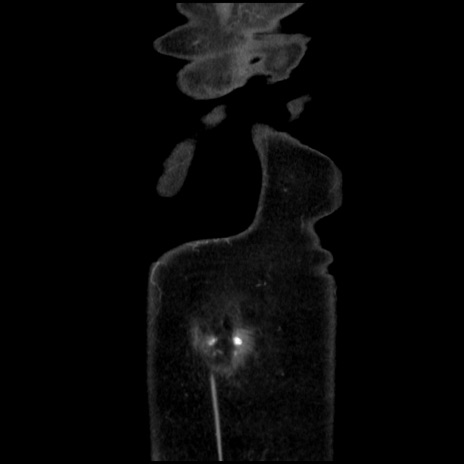

症例32(冠状断像)

横断像

矢状断像